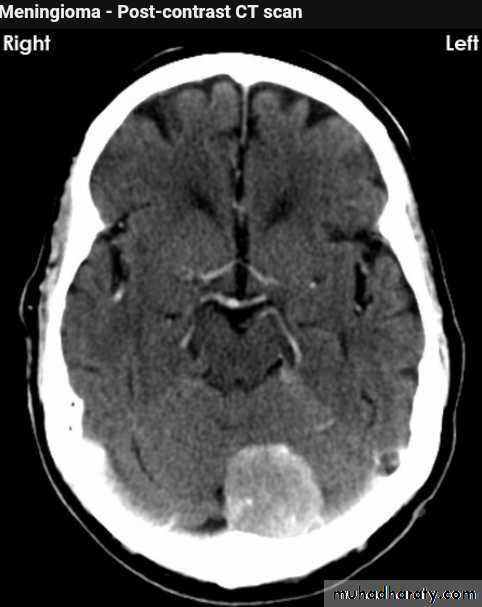

Meningioma

Benign tumor arise from the arachnid cells of the meningeal covering of the brain are most common primary intracranial neoplasm

Usually present in middle age female

it is well defined extra axial , located mainly at the convexity of the skull periphery

rounded or sessile , plaque like , specially the tumor arise from the cribriform plate , or those arise from the petrus bone , planum spheniodale , or from skeleton of the pituitary fosse .

CT finding

meningioma presented as isodense area or slightly hyper density area with surrounded crescent of hypo density ( csf cap ) post contrast injection the lesion enhance homogeneously with enhancing Dural tail .

20 % show calcification

hyperostosis & thickening of the near by bony part of the skull & diplioc space .

it may be associated with little or no peri focal edema .

if the lesion associated with central necrosis with large perifocal edema meningio sarcoma should be excluded .